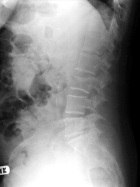

S.L. - 66 year old woman with a history of sarcoidosis and polycythemia vera with low back pain for two months and acute left shoulder pain after opening a window

Zoom image: Radiological image Radiological image.